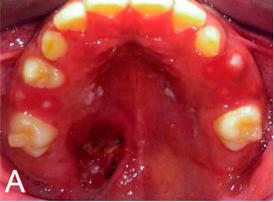

El adenoma pleomorfo es la neoplasia benigna más común de las glándulas salivales. Su localización común está en glándula parótida, sin embargo, un bajo porcentaje de estos tumores puede ocurrir en glándulas menores. La epidemiología de este tumor muestra que los adultos son los más afectados, con rara ocurrencia en niños o adolescentes. Presentamos el caso de un adenoma pleomorfo localizado en el paladar de un niño de 10 años. La biopsia excisional de la lesión seguida de examen histopatológico de la muestra de biopsia reveló estructuras ductales rodeadas por células mioepiteliales plasmocitóides dentro de un estroma mixoide, siendo el diagnóstico final adenoma pleomorfo. La detección temprana y la excisión de esta lesión en los niños es importante para minimizar las recidivas potenciales o la transformación maligna. Información del paciente: Infante masculino de 10 años acude a la clínica de la Facultad de Odontología, Universidad Mesoamericana sede Quetzaltenango para tratamiento odontopediátrico. Dentro de la historia clínica no refiere antecedentes de importancia. Al examen intraoral se evidenció nódulo ovoide, ubicado en tercio posterior derecho de paladar duro, base sésil, consistencia blanda, un poco más pálido que la mucosa adyacente, superficie lisa, asintomático y de evolución desconocida (Figura 1). No se evidenció compromiso óseo en el estudio radiográfico. Bajo esta descripción se hizo diagnóstico presuntivo de Adenoma Pleomorfo. Se realizó biopsia incisional central y el diagnóstico preliminar fue Adenoma Pleomorfo. Se indicó excisión quirúrgica de la lesión para confirmar el diagnóstico.

2b, 2c). El resultado histopatológico de la muestra enviada presentó los siguientes hallazgos: presencia de una mezcla de epitelio glandular y abundantes islas con aspecto de células mioepiteliales plasmocitoides con formaciones ductales inmersas en un estroma mixoide, se aprecia formación parcial de cápsula fibrosa (Figura 3). Se determinó como diagnóstico histopatológico Adenoma Pleomorfo. Discusión: Las neoplasias de glándulas salivales menores en niños son raras. Se menciona que solo el 5% de estos han sido reportadas en pacientes menores de 20 años (Moubayed et al., 2010). El diagnóstico de AP palatal es un verdadero reto porque puede confundirse con otras entidades como quistes o tumores odontogénicos, abscesos palatinos, linfoma, lipoma, fibroma, neurofibroma, neurilemoma (schwannoma), carcinoma mucoepidermoide o incluso carcinoma adenoide quístico (Hmidi et al., 2015; Sreenivas, 2011). La epidemiología de esta neoplasia indica que es más frecuente en pacientes del sexo femenino con una proporción de 2:1 en la cuarta y quinta década de la vida, en nuestro caso el paciente tenía 10 años lo que merece una mención especial ya que esta neoplasia afecta generalmente a adultos. (Barnes et al., Histológicamente2005).